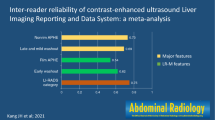

Forty-three lesions were HCCs; two were intrahepatic cholangiocarcinomas; five were benign lesions. Arterial phase hyperenhancement was perceived less frequently with CEUS than with MRI (37/50 / 38/50 lesions = 74%/78% [CEUS; observer 1/observer 2] versus 46/50 / 44/50 lesions = 92%/88% [MRI; observer 1/observer 2]). Washout appearance was observed in 34/50 / 20/50 lesions = 68%/40% with CEUS and 31/50 / 31/50 lesions = 62%/62%) with MRI. Interobserver agreement was moderate for arterial hyperenhancement (ĸ = 0.511/0.565 [CEUS/MRI]) and “washout” (ĸ = 0.490/0.582 [CEUS/MRI]), fair for CEUS-LI-RADS category (ĸ = 0.309) and substantial for MRI-LI-RADS category (ĸ = 0.609). Intermodality agreement was fair for arterial hyperenhancement (ĸ = 0.329), slight to fair for “washout” (ĸ = 0.202) and LI-RADS category (ĸ = 0.218)

Interobserver agreement is substantial for MRI-LI-RADS and only fair for CEUS-LI-RADS. This is mostly because interobserver agreement in the perception of washout appearance is better in MRI than in CEUS. Further refinement of the LI-RADS algorithms and increasing education and practice may be necessary to improve the concordance between CEUS and MRI for the final LI-RADS categorization.

• With CEUS, interobserver agreement is better for arterial hyperenhancement than for “washout”.

• Interobserver agreement for major features is moderate for both CEUS and MRI.

• Interobserver agreement for LI-RADS category is substantial for MRI, and fair for CEUS.

Interobserver agreement according to Cohen’s kappa was moderate for arterial phase hyperenhancement (ĸ = 0.511) and washout appearance (ĸ = 0.490), and fair for the CEUS-LI-RADS category (ĸ = 0.309) (Table 5).

Interobserver agreement for MRI-LI-RADS was moderate for capsule appearance (ĸ = 0.449), arterial phase hyperenhancement (ĸ = 0.565) and washout appearance (ĸ = 0.582), and substantial for the LI-RADS category (ĸ = 0.609, Table 5).

Our study is the first one to assess interobserver agreement for MRI-LI-RADS and CEUS-LI-RADS in direct comparison. We found moderate interobserver agreement for MRI-LI-RADS for all three major features (arterial phase hyperenhancement, washout appearance, capsule appearance) and substantial agreement for MRI-LI-RADS category. With CEUS-LI-RADS we found moderate interobserver agreement for arterial phase hyperenhancement (ĸ = 0.511) and washout appearance (ĸ = 0.490) and only fair agreement concerning CEUS-LI-RADS category (ĸ = 0.309). Importantly, intermodality agreement between CEUS and MRI was only fair for arterial phase hyperenhancement (κ = 0.329), slight to fair for “washout” (κ = 0.202) and slight to fair for LI-RADS category (κ = 0.218). The fact that interobserver agreement for the final category was substantial for MRI and only fair for CEUS although interobserver agreement for major features was moderate for both modalities might be due to the fact that “washout” plays a more important role in MRI than in CEUS.